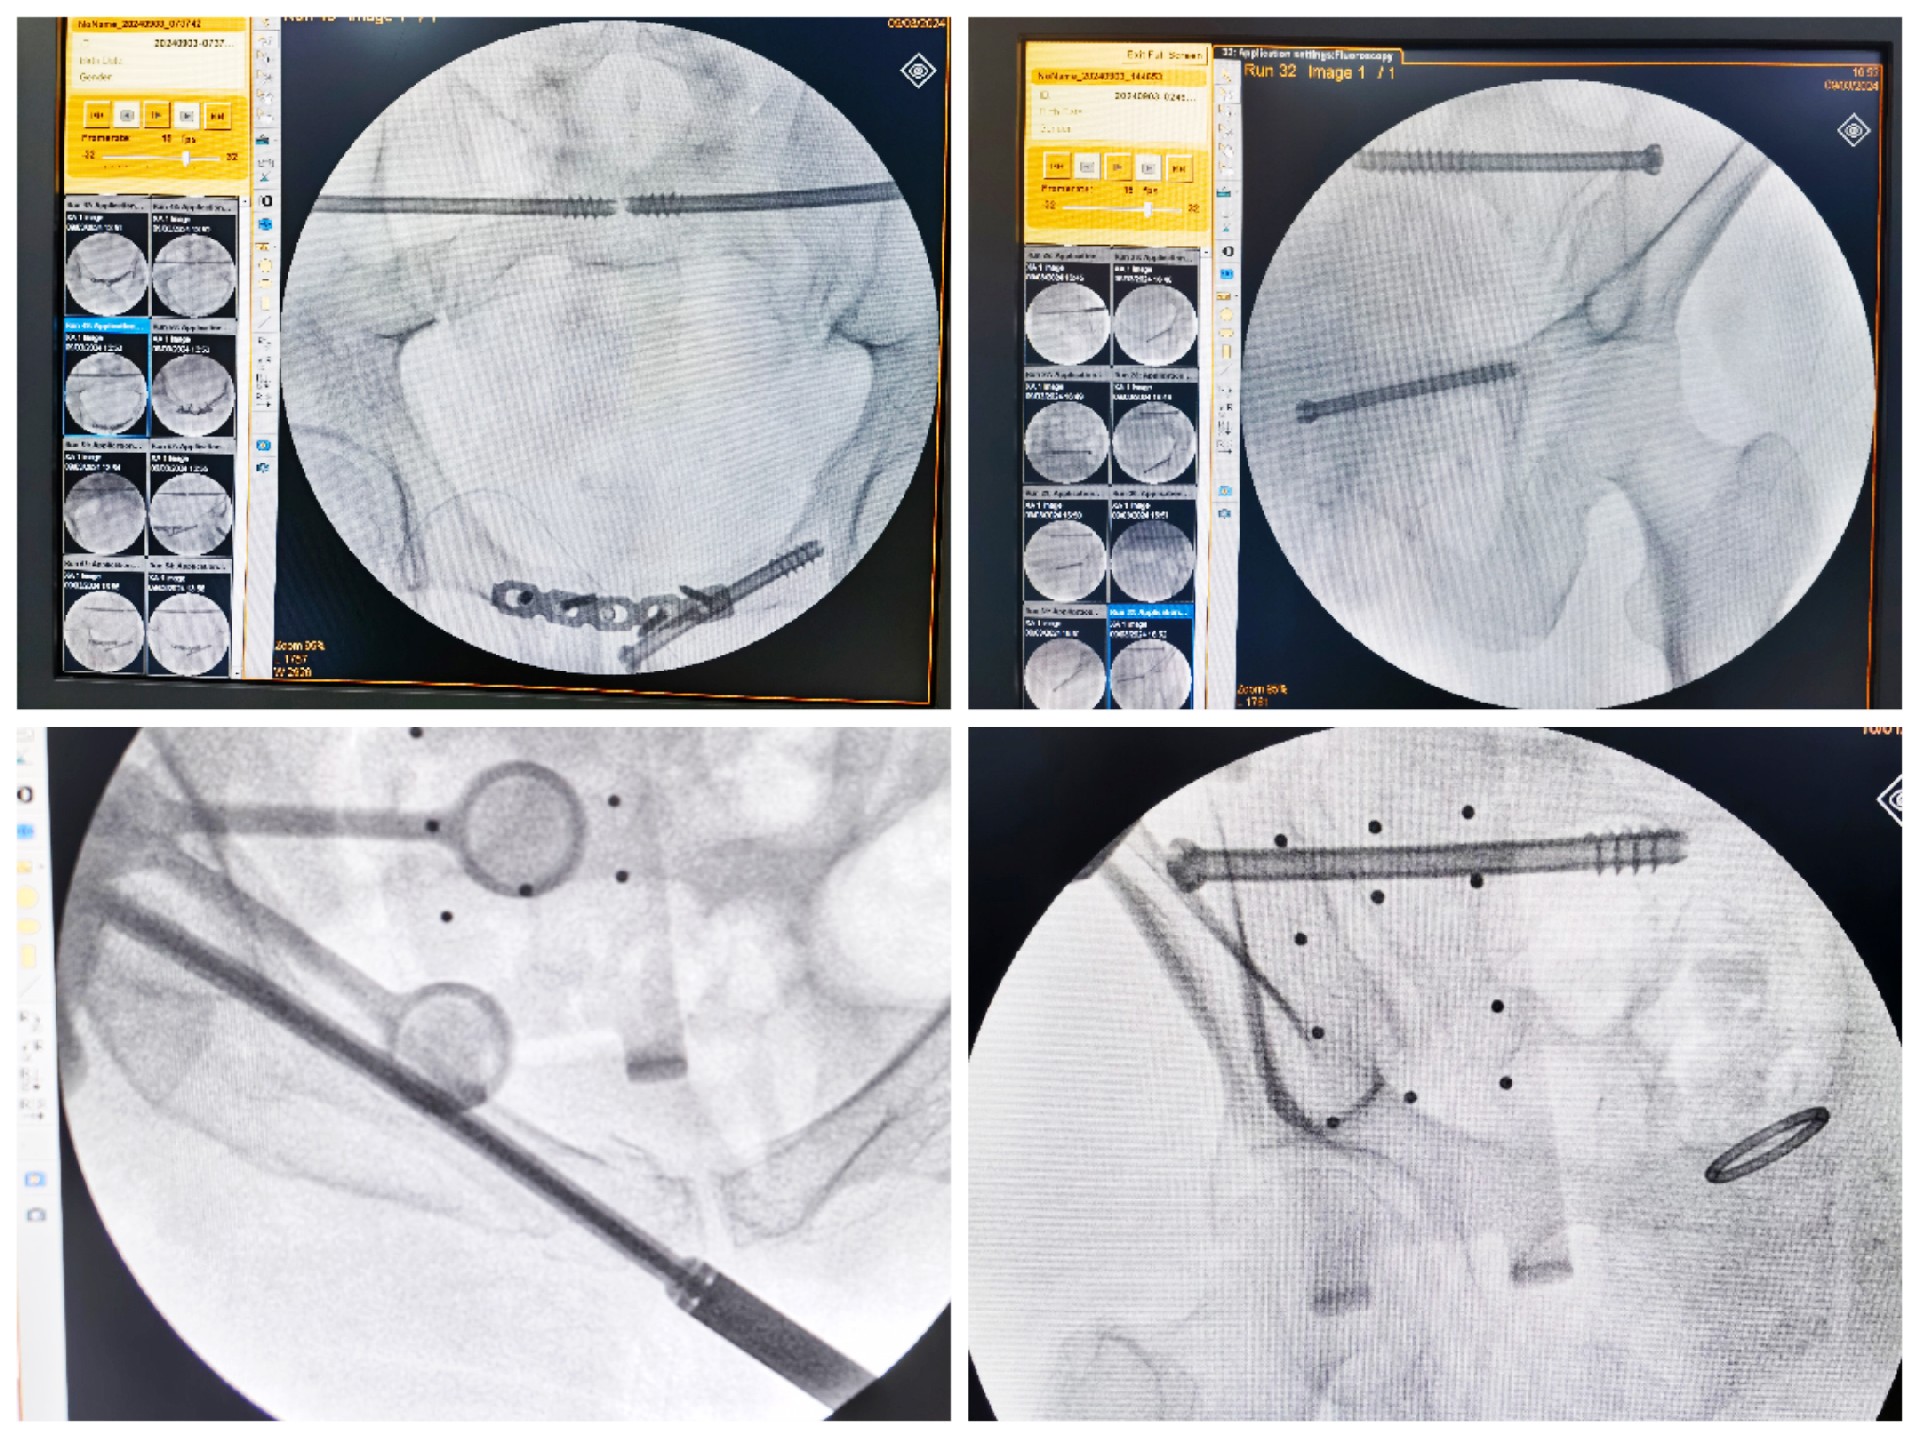

傳統(tǒng)的骨盆骨折微創(chuàng)手術(shù)中,骶髂螺釘?shù)嚷葆斨萌氲碾y點(diǎn)在于骨盆部位解剖十分復(fù)雜,螺釘置入如有偏差極易損傷重要神經(jīng)及血管,手術(shù)不僅依靠手術(shù)醫(yī)師豐富的經(jīng)驗(yàn),還需要術(shù)中反復(fù)的C型臂透視及調(diào)整,對(duì)患者及醫(yī)生都有較大輻射。而利用HoloSight知見創(chuàng)傷骨科機(jī)器人進(jìn)行骨盆骨折微創(chuàng)手術(shù),通過高精度光學(xué)定位追蹤技術(shù)與混合現(xiàn)實(shí)技術(shù),使整個(gè)微創(chuàng)手術(shù)全程可視化,可以在電腦屏幕上實(shí)時(shí)顯示螺釘?shù)木珳?zhǔn)置入位置,降低手術(shù)風(fēng)險(xiǎn),提高手術(shù)效率及安全性。

術(shù)前,手術(shù)團(tuán)隊(duì)認(rèn)真分析討論病例,全面掌握骨盆骨折微創(chuàng)治療的關(guān)鍵技術(shù),提前設(shè)計(jì)手術(shù)方案并反復(fù)模擬演練手術(shù)過程。術(shù)中,利用HoloSight知見創(chuàng)傷骨科機(jī)器人規(guī)劃骨折復(fù)位方案及定位螺釘通道,實(shí)現(xiàn)精準(zhǔn)微創(chuàng)手術(shù)。手術(shù)通過不足1cm小切口完成,最大程度地減少了術(shù)中出血,術(shù)中幾乎都是一次性成功精準(zhǔn)微創(chuàng)地置入內(nèi)固定螺釘,減少了醫(yī)源性操作對(duì)骨折周圍骨質(zhì)的影響,實(shí)現(xiàn)骨折微創(chuàng)固定的同時(shí)盡可能提高骨折固定的穩(wěn)定性,為術(shù)后患者的快速康復(fù)創(chuàng)造了有利條件。